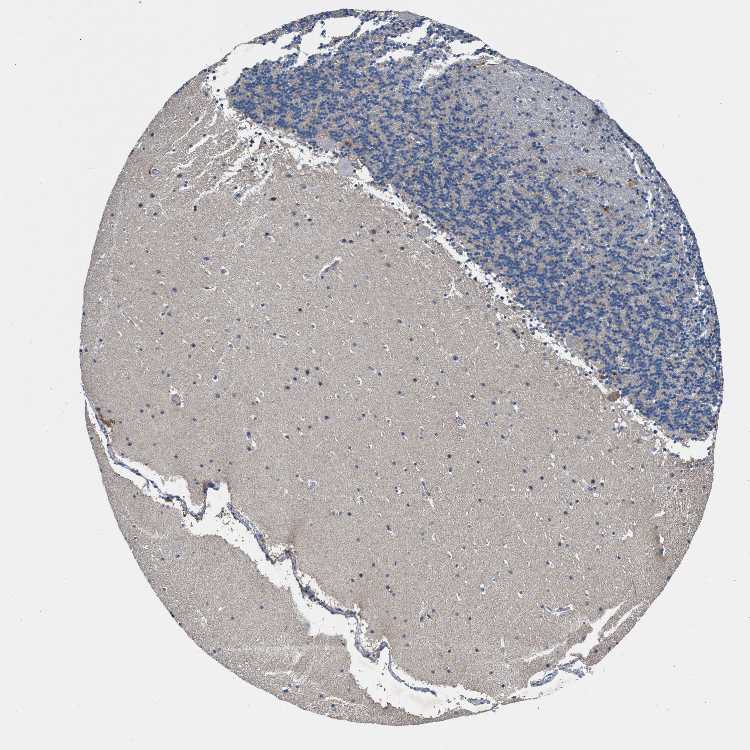

CEREBELLUM - Antibody stainingi

Antibody staining in the annotated cell types in the current human tissue is reported as not detected, low, medium, or high, based on conventional immunohistochemistry profiling in selected tissues. This score is based on the combination of the staining intensity and fraction of stained cells.

Each image is clickable and will lead to virtual microscopy that enables deeper exploration of all samples and also displays staining intensity scores, fraction scores and subcellular localization as well as patient and tissue information for each sample.

Antibody HPA021590

Purkinje cells Medium

Cells in granular layer Not detected

Cells in molecular layer Not detected